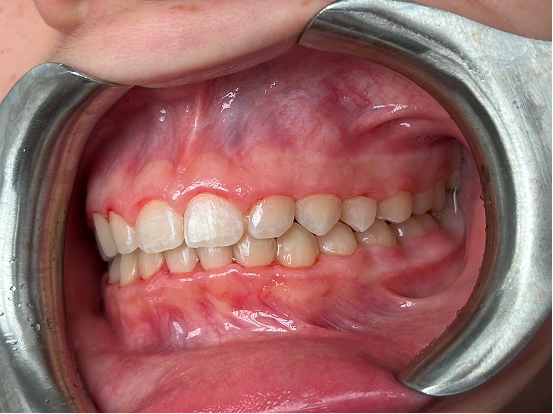

Braces GI

GI achieved a beautifully balanced smile through braces treatment. Over time, the brackets and wires gently moved each tooth into its ideal position, resulting in improved alignment, comfort, and confidence in their everyday smile.